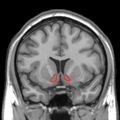

- Basal ganglia

- Includes: Nucleus caudatus, putamen, pallidum, subthalamus, substantia nigra

- Part of the forebrain.

- Caudate nucleus + putamen = striatum.

- Pallidum + putamen = lenticular nucleus.